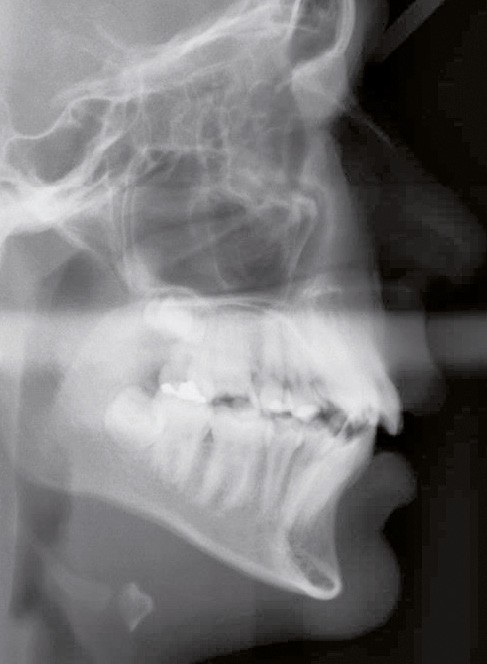

En denture adulte, la DDM est majeure avec un déficit de place estimé de 13 mm à la mandibule. Les lésions carieuses ont aussi touché les premières molaires permanentes maxillaires. La 26 a été avulsée et la 27 a pris sa place. Côté controlatéral, la 16 est fortement délabrée, rendant impossible sa conservation. Les molaires ayant plus mésialé à l’arcade mandibulaire, les rapports occlusaux sont de classe III. Les incisives sont versées vers l’avant, mais nous pouvons considérer qu‘il s’agit d’une biproalvéolie ethnique. Du point de vue squelettique, le patient présente une classe II squelettique par rétromandibulie sur un schéma facial hyperdivergent (fig. 1a-j).